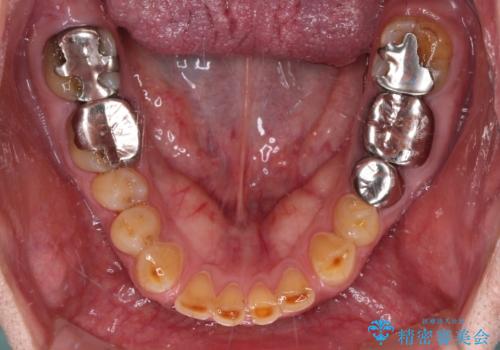

診察をしたところ、上下大臼歯の歯肉に排膿路認められたため、根管治療を行い、その後補綴治療を行うこととしました。

下顎大臼歯の抜歯決断までに時間がかかったため、治療期間はやや長くなりましたが、安定した咬み合わせとなり、痛みもなく安心して噛めるようになりました。